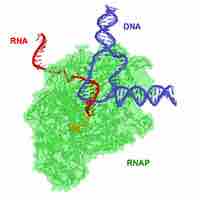

Antimicrobial drugs inhibit nucleic acid synthesis through differences in prokaryotic and eukaryotic enzymes.